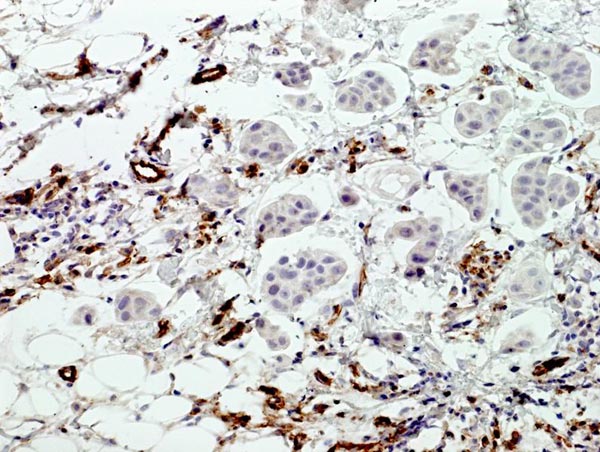

Obr. 3

Arteficielní dutiny nejsou vystlané endotelem (CD 34 pozitivní jen v kapilárách)